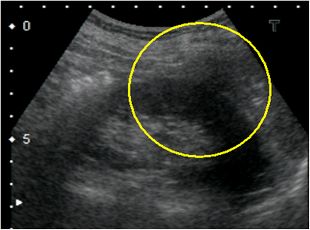

当院では、高精度画像診断によって、より早期の段階で腎がんを診断することに努めています。小さな腎腫瘍においては、しばしば良性腫瘍とがんの鑑別が難しいことがありますので、腹部超音波検査、CT検査MRI検査、また血管造影検査を組み合わせて、総合的に診断を行います。

超音波検査